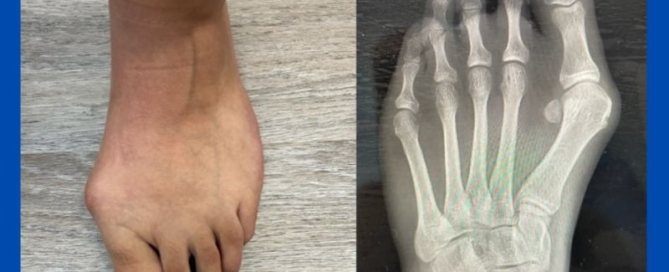

Juvenile hallux valgus (bunion)

Blog's main page This case shows just how strong genetics can play in the development of bunions. This is the foot of a 16-year-old. The parents and podiatrist have been [...]